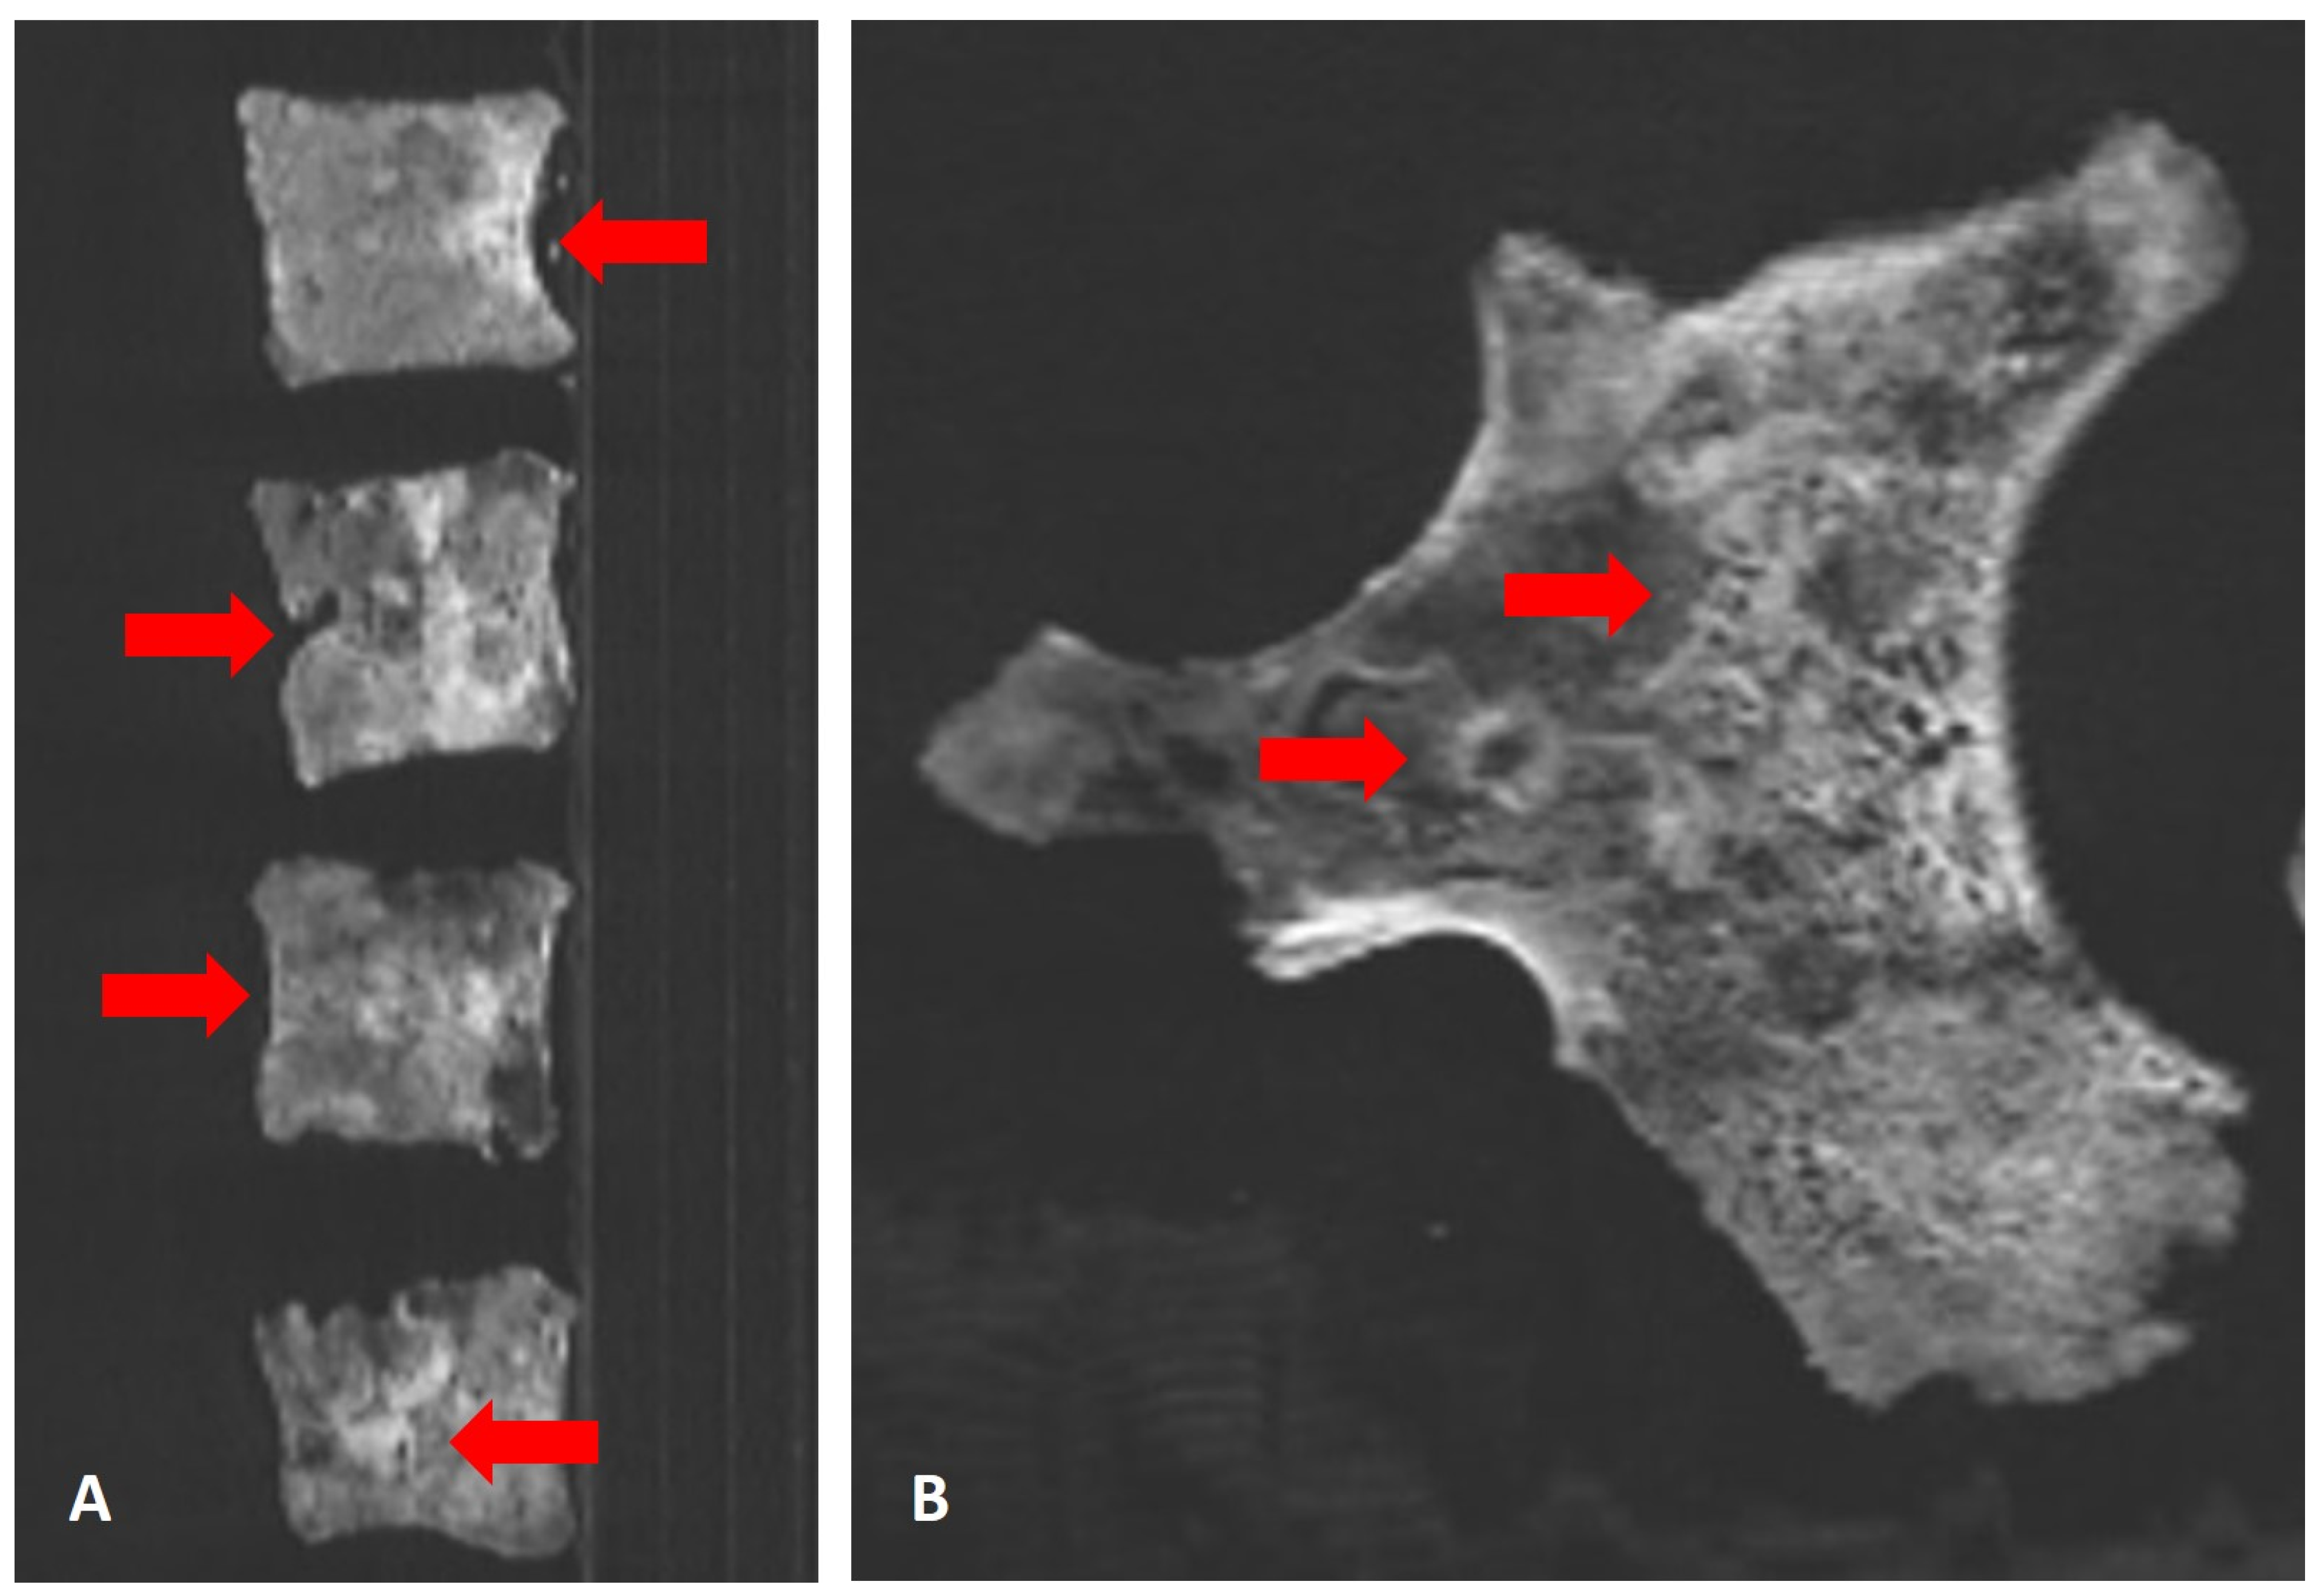

3.3. CT-scans

The scanning of all available bones confirmed the macroscopic observations. All preserved vertebral bodies and the fragments of both hemipelvises showed widespread mixed osteolytic-osteoblastic bone defects highly suggestive of multiple osseous metastases (Figure 8A, B). Additionally, isolated, mostly osteolytic lesions were seen in the skull, mainly lacking the osteoblastic component (Figure 8C). In addition, the CT scans showed additional metastatic infiltration in the left temporo-mandibular joint which was macroscopically unremarkable (Figure 8D). In contrast, long bones and the few small bones of the feet remain free of abnormal lesions. In general, the mineralisation of the skeleton was fairly well preserved with no signs of significant generalised osteopenia.

Figure 8. CT scans of the osteolytic-osteoblastic lesions of the skeleton: A) Sagittal reconstruction through several vertebral bodies showing the extensive mixed osteolytic-osteoblastic bone reaction (arrows). B) Paracoronal reconstruction through the right pelvic bone fragment also showing extensive mixed bone infiltration (arrows). C) Parasagittal reconstruction through the skull with a circumscribed osteolysis, mainly of the inner skull bone table (arrows). D) Axial reconstruction through the skull showing an additional presumed metastasis in the left temporomandibular joint (circle); note the soil residues in the maxillary sinus (arrows) (images: S. Panzer).